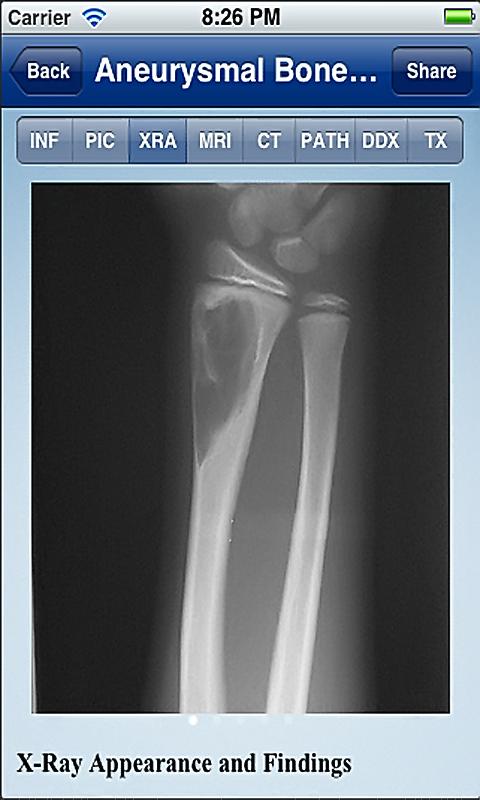

Cada aplicación Tumorpedia contiene información sobre 20 a 50 tumores diferentes, que abarcan la etiología, patogenia, presentación clínica y hallazgos de la exploración, así como la radiografía, resonancia magnética y tomografía computarizada de la aparición del tumor. Las características diagnósticas de cada tumor se ilustran con cientos de imágenes de ejemplos de casos reales. Además, los resultados de patología microscópicas se describen e ilustran. La aplicación ofrece opciones de tratamiento, información de los resultados y el pronóstico para cada tumor.